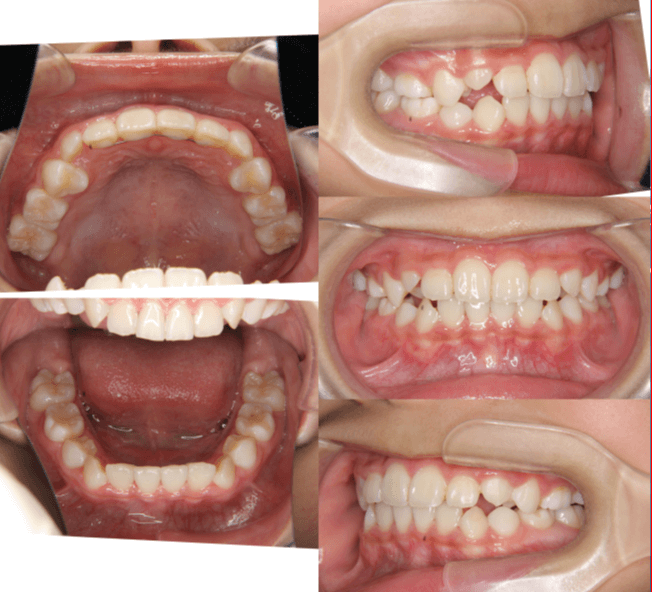

上歯前突+叢生症例 成長期

主訴 | 口元の突出感と歯並びが気になり、将来的な咬合状態を整える目的で来院された患者様です。 |

---|---|

診断結果 | 11歳1か月の女性。骨格的には日本人標準に近く、歯性の上顎前突および叢生が認められました。上下顎ともに歯列のスペース不足があり、永久歯の萌出や歯列の整列に支障をきたす可能性があると診断されました。 |

治療内容 |

|

治療後の経過 | 動的治療終了後は、上下顎の歯列が整い、口元の突出感と叢生が改善されました。審美的・機能的なバランスが取れた状態となり、現在は取り外し式リテーナーを使用し、保定期間に移行しています。 |

治療期間 | 動的治療期間:2年6か月 通院回数:25回 |

治療費用 | 720,000円 |